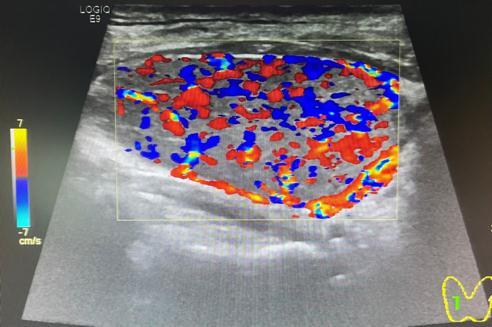

毒性弥漫性甲状腺肿(Graves病):大多为均匀性肿大,也有表现为非均匀性肿大的(较少),通常表现为腺体弥漫性低回声。很多患者就因为发现脖子肿大来就诊。毒性弥漫性甲状腺肿最典型的超声表现为“火海征”,即甲状腺的血供异常丰富,甲状腺上动脉通常都有增宽,一般超过2mm,流速增快。

图片